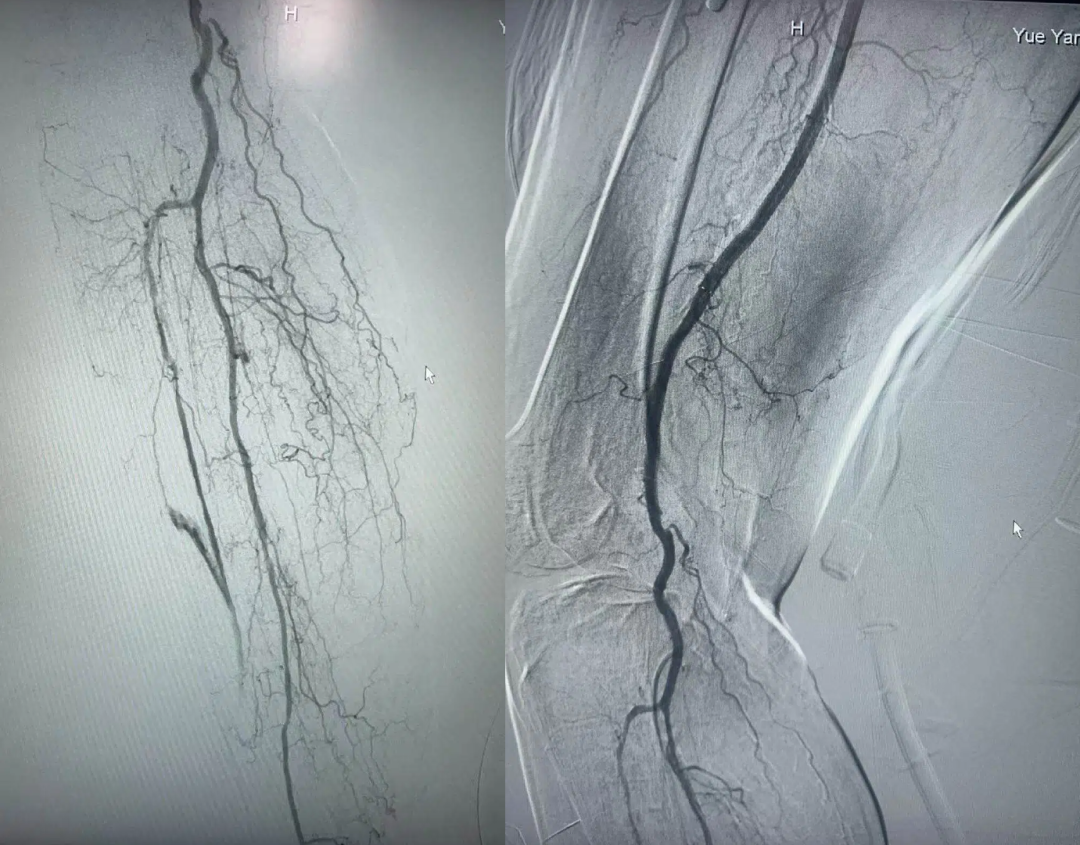

术后影像

我院骨显微/创面修复科团队为老人定制个性化方案,实施高选择性下肢动脉造影+球囊扩张成形术+支架植入术:精准穿刺定位狭窄血管,球囊扩张后植入自膨式镍钛合金支架,成功打通堵塞血管,术后老人静息痛即刻缓解,皮温回升,溃疡渗液减少,血供恢复正常,成功挽救患肢!